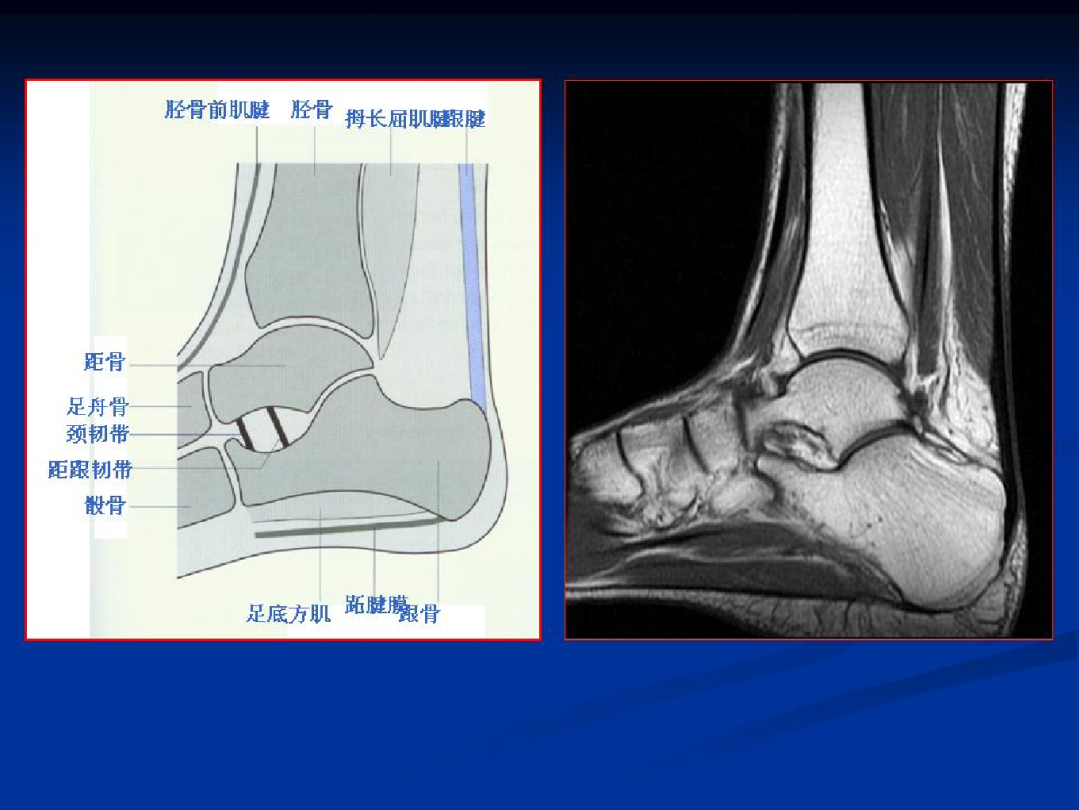

肌腱

外侧:腓骨长肌腱、腓骨短肌腱

内侧:胫骨后肌腱、趾长屈肌腱、踇长屈肌腱

前方:胫骨前肌腱、趾长伸肌腱、踇长伸肌腱

后方:跟腱